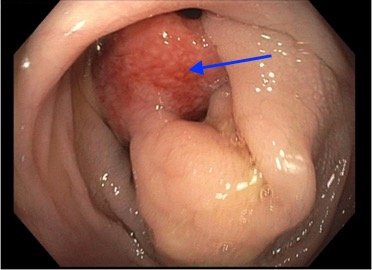

Intussusception is the telescoping of bowel into an adjacent segment of bowel and has an associated risk for bowel ischemia and perforation. The classic triad of abdominal pain, blood in stool, and an abdominal mass is present in less than 40% of pediatric cases and is less common in older children.1 Ultrasound has a high sensitivity and specificity for the diagnosis of intussusception, and once diagnosed, treatment modalities include reduction by either ultrasound or fluoroscopic guided air or hydrostatic enema. The risk of recurrence after successful reduction occurs in up to 12% of pediatric patients and occurs more frequently in older children and children with a pathologic lead point.2 We present a case of a 6-year-old child with colocolic intussusception that was successfully reduced and recurred within five days due to a large colonic polyp.